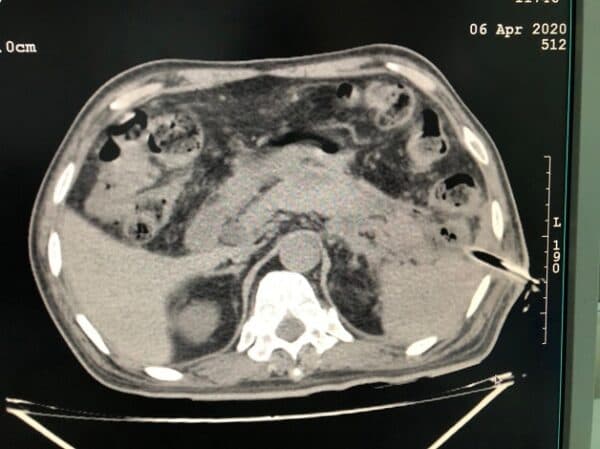

Hình ảnh tổ chức viêm ở tụy dưới hình ảnh CT

Viêm tụy hoại tử là hiện tượng hoại tử quanh tụy hoặc hoại tử tụy. Hình ảnh hoại tử tụy sẽ dễ quan sát hơn dưới hình ảnh CT có tiêm thuốc cản quang. Tình trạng viêm tụy hoại tử xuất hiện ở 5 – 10% số bệnh nhân viêm tụy, tiên lượng khá nặng.

Tổn thương do viêm tụy cấp có thể thấy rõ ràng hơn dưới hình ảnh CT có tiêm thuốc cản quang

– Trên hình ảnh CT có tiêm thuốc cản quang, xuất hiện những ổ hoại tử.